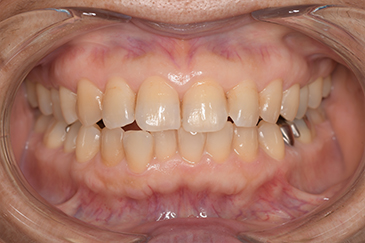

クリーニングの症例

現在の治療費と異なる場合がございます。最新の治療費は料金表をご確認ください。CASE 1

Before

After

基本情報

| 主訴 | 見た目をきれいにしたい |

| 治療期間 | 6ヶ月 |

| 治療費 | ジルコニアボンド(セラミックの被せもの)¥165,000×7(税込み) オフィスホワイトニング4回 ¥4,400×4(税込み) ホームホワイトニング¥11,000 |

| リスク・副作用 | かみ合わせがとても強い方の場合、稀に割れてしまうことがあります。 |

| 先生からの提案 | 上の前歯6本と右下の2番目の歯はセラミックの被せもので治療。 残りの下の前歯5本はプラスチックの材料で虫歯を治療し、 ホワイトニングをおこないました。白くなったご自身の歯の色に合わせてセラミックの 被せものを作成しています。 模型上で完成後をシュミレーションし、上の歯茎の位置をきれいに見えるように 揃えています。(外科処置はしていません) |